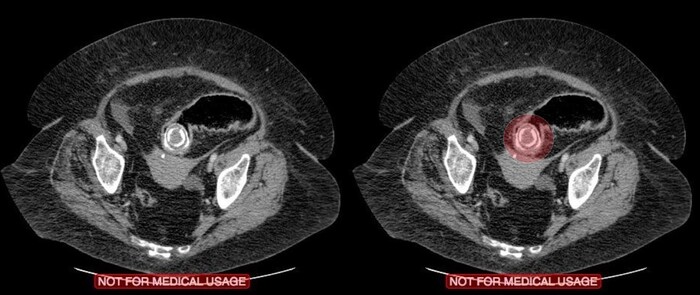

На 3й день после травмы из комы так и не вышла, посему сделали МРТ, на котором обнаружились участки повышенного сигнала на Т2-взвешенных изображениях на границе серого и белого вещества фронтально и темпорально справа, а также в область правого таламуса и в заднем отделе мозолистого тела т.н. сплениуме:

которые визуализировались и на FLAIR:

Очаги показывали также ограниченную диффузию на DWI-изображениях:

Ну и в довесок на SWI-изображениях (специальная импульсная последовательность, взвешенная по магнитной восприимчивости, усиливает сигнал от продуктов распада гемоглобина, что значительно повышает способность распознавать мельчайшие кровоизлияния в головном мозге) были выявлены очаги микрокровоизлияний в поражённых участках + в верхней ножке мозжечка и вдоль кортико-спинального тракта справа (чёрные пятна на изображениях):